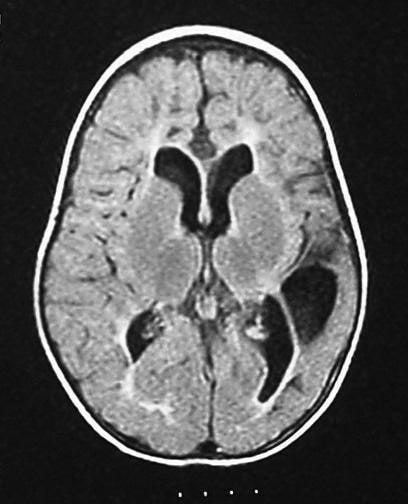

Cerebral palsy is a type of neurological disorder that results due to some damage to the brain which results in motor and movement related disability in childhood. This condition usually presents with some combination of the following manifestations: - Hand preference before 1 year of age - Crawling is asymmetrical or not possible at all - Exaggerated reflexes - Absence or underdevelopment of protective or postural reflexes. The injury the leads to this condition could have occurred at any point in time during during the foetal development. The major causes that can be higlighted include: - genetic abnormalities - toxic or infectious cause - vascular insufficiency, e.t.c Text Reference and Image Source: https://emedicine.medscape.com/article/1179555-overview